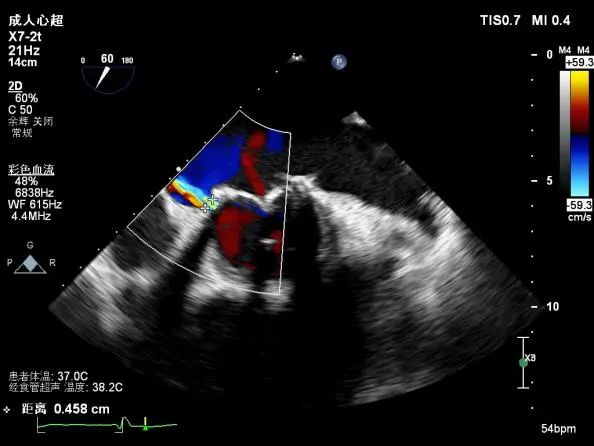

升主动脉管壁回声增强;主肺动脉增宽。二尖瓣位生物瓣瓣架固定,瓣叶增厚、回声增强,局部粘连,致瓣叶开放受限(PHT法测有效瓣口面积约0.9-1.1cm²)、关闭欠佳,瓣叶与内侧瓣架见探及缝隙约3-4mm。三尖瓣位生物瓣瓣架固定,瓣尖增厚、回声增强,稀叶启闭尚可,瓣叶与内侧、外侧瓣架分别探及缝隙约3mm、1mm。主动脉瓣关闭欠佳:余瓣膜形态、结构未见明显异常。

二尖瓣间隔侧探及封堵器1枚,位置固定,原生物瓣与室间隔间裂隙消失。